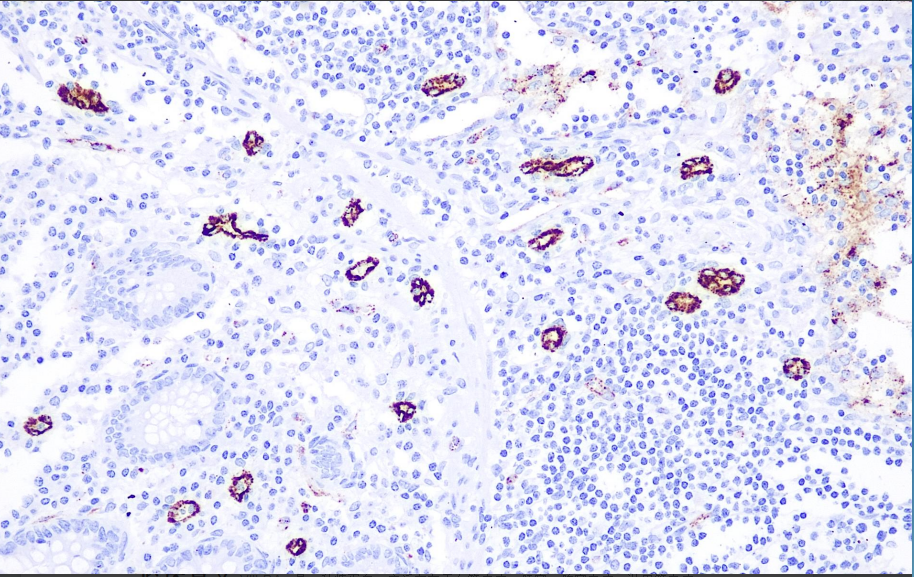

阳性对照: 阑尾

Ⅷ因子相关抗原存在于人的血管内皮细胞、巨核细胞和血小板。此抗体可以用于血管源性良性和恶性肿瘤的诊断,血管外皮细胞瘤常阴性表达。由于其也存在于正常的血浆和血小板中,在出血或血管损伤部位必有阳性着色,所以应注意区分。

Factor Ⅷ抗体试剂可与Factor Ⅷ分子抗原特异性结合,含Factor Ⅷ抗体试剂的免疫组化试剂盒适用于血管内皮良恶性肿瘤和血管肉瘤的精准诊断。